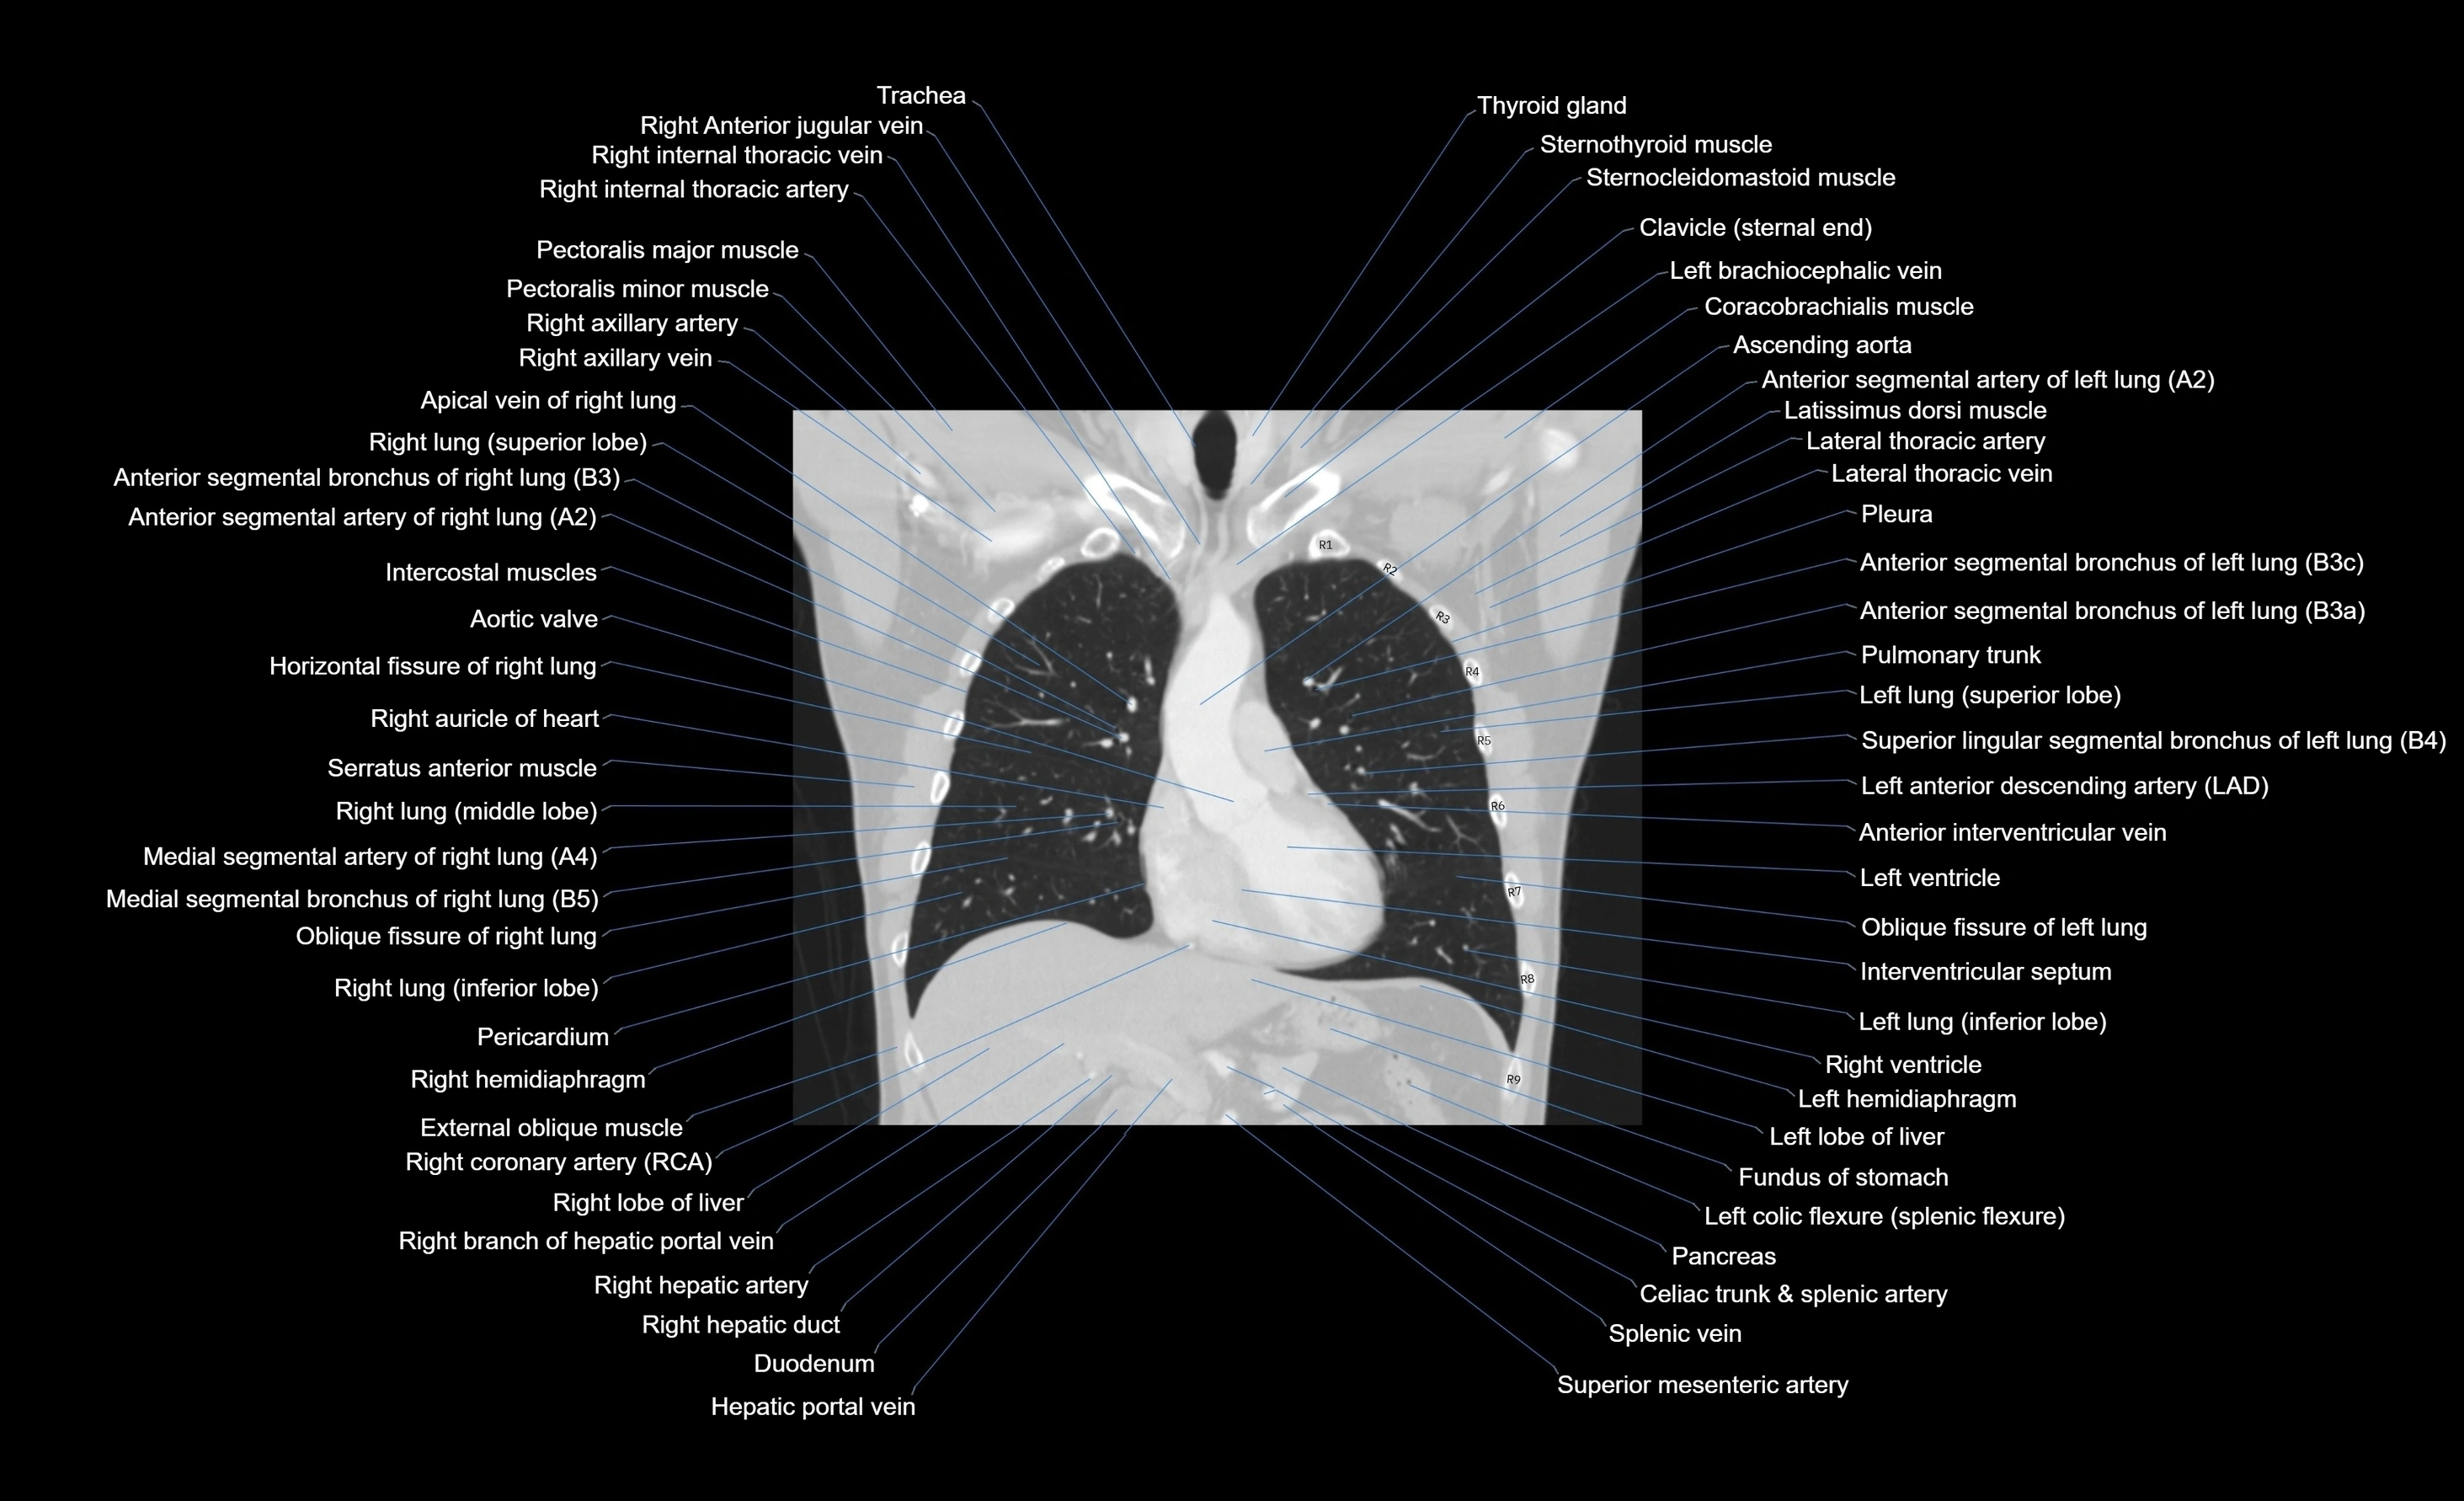

- Ascending aorta

- Hepatic portal vein

- Left anterior descending artery (LAD)

- Left hemidiaphragm

- Left lobe of liver

- Pancreas

- Pectoralis major muscle

- Pectoralis minor muscle

- Pulmonary trunk

- Right lobe of liver

- Thyroid gland

- Trachea